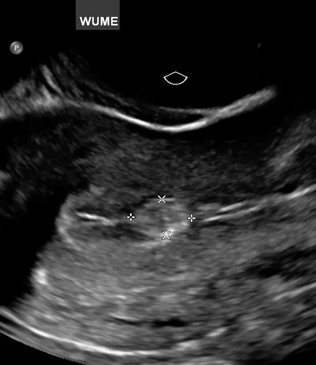

Gynecology ultrasound is a diagnostic imaging technique used to examine the female reproductive organs, including the uterus, ovaries, cervix, and surrounding pelvic structures. It uses high-frequency sound waves to produce clear images of these organs, helping doctors identify and evaluate various gynecological conditions.

- Transvaginal ultrasound for detailed pelvic imaging

- Images of reproductive organs are displayed on a monitor

- The doctor evaluates the structures and measurements